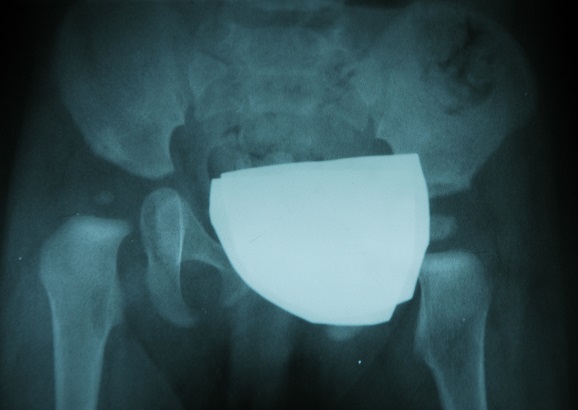

w razie jakichkichkolwiek watpliwosci od 3 miesiaca zycia ;badanie RTG jest konieczne.